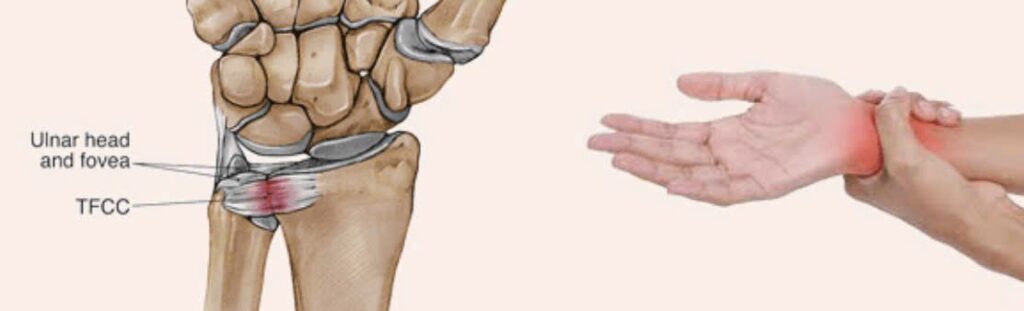

(TFCC – Triangular Fibrocartilage Complex Tear)

Phức hợp sụn sợi tam giác (TFCC) là phức hợp gồm sụn, dây chằng và gân nối xương quay với xương trụ và các xương ở cổ tay.

Đây là một cấu trúc hoạt động như một bộ phận giảm xóc; giúp tạo độ ổn định, vững chắc cho cổ tay trong các hoạt động xoay vặn.

Phức hợp sụn sợi tam giác là một tấm sụn được căng từ mặt ngoài mỏm trâm trụ tới bờ dưới khuyết trụ xương quay. Có thể chia làm 3 phần

- Phần đĩa sụn sợi hình tam giác

- Dây chằng quay trụ

- Phức hợp dây chằng trụ – cổ tay